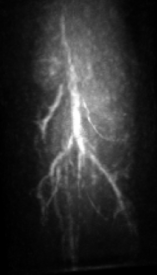

V.3 Experimental results

The maximum intensity projection (MIP) of the 3D mouse images reconstructed by use of the GPU-based implementations reveal the mouse body vasculature as shown in Fig. 7. Images reconstructed by use of both the PLS-Int and the PLS-Sph algorithms appear to have cleaner background than do the images reconstructed by use of the FBP algorithm from the same amount of data. All images reconstructed by iterative algorithms were obtained by 202020-iterations starting with uniform zeros as the initial guess. The PLS-Int algorithm took approximately a half day and 222 days to process the “quarter data” and the “full data” respectively. The PLS-Sph algorithm took approximately one day and 444 days to process the “quarter data” and the “full data” respectively. Alternatively, if the CPU-based implementations were utilized, the PLS-Int algorithm would take an estimated 686868 days and 277277277 days to process the “quarter data” and the “full data” respectively. The PLS-Sph algorithm would take an estimated 275275275 days and 1,10011001,100 days to process the “quarter data” and the “full data” respectively.